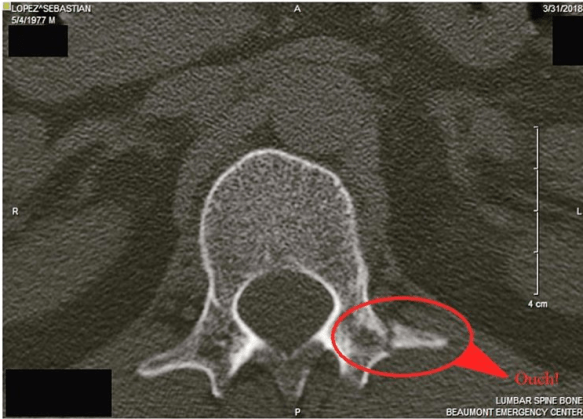

Who needs toenails anyways?1?!